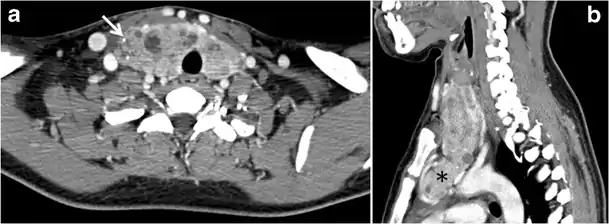

Goiter

A goiter is an abnormal thyroid gland proliferation that manifests as multi-nodular, uni-nodular, or non-nodular diffuse glandular enlargement. A goiter is formed of solid matrix, colloid cysts, blood products, calcification, and fibrosis, and this heterogeneity may lead to variable appearances on a CT scan (Figs. 13, 1414 and and15)15). The US is more sensitive in evaluating thyroid nodules within a goiter; however, a symptomatic goiter may require surgical treatment with total thyroidectomy, and in this case CT plays an additional role in preoperative evaluation. Specific aspects for examination on a CT scan during the preoperative evaluation for goiter include extension, mass effect, and suspicious features of malignancy.[1]

Fig. 13. A 27-year-old female patient known to have goiter. a, b Axial and sagittal enhanced CT scan images of the neck demonstrate a heterogeneously enhancing, enlarged thyroid gland with scattered calcifications (white arrow), cystic changes, and substantial retro-sternal extension (black asterisks). No lymphadenopathy or substantial airway narrowing.[1]

Malignancy can coexist within the goiter and a CT scan may give a clue if there are abnormal cervical lymph nodes and/or signs of invasion. Retrosternal extension (Fig. 15) could affect the surgical approach, as a lower extent may require a partial or total sternotomy to facilitate complete resection. Therefore, the distance of the retrosternal extent from the sternal notch should be measured on a sagittal image.[1]

The interpreting radiologist should describe the mass effect, detailing its degree and direction of displacement of central structures, including the trachea, oesophagus, larynx, and pharynx. Attention should be directed to the upper extent of the goiter and structures immediately surrounding the thyroid gland, including the neuro-vascular structures, retropharyngeal space, and pre-vertebral space. The reporting radiologist should evaluate the vocal cords for symmetry and signs of vocal cord palsy.[1]